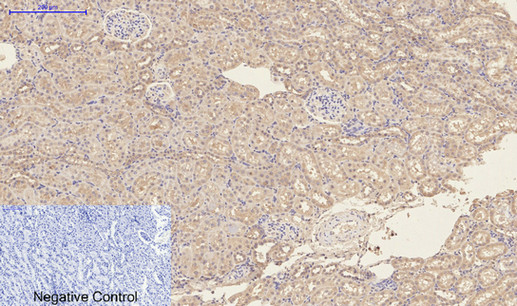

Product Image |

| IHC | 1/50-1/100 |

| ICC | 1/50-1/200 |

Mouse Monoclonal Antibody to CD23

| This receptor has essential roles in the regulation of IgE production and in the differentiation of B-cells (it is a B-cell-specific antigen). | |

| Species Reactivity | Human,Mouse,Rat |